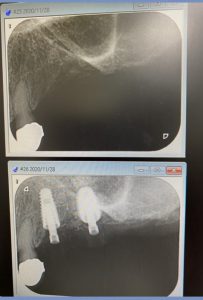

午後の方は、洞底皮質骨に絡み値も良く即時荷重非接触の仮歯まで装着しました。

(オペ後、仮歯装着まで)